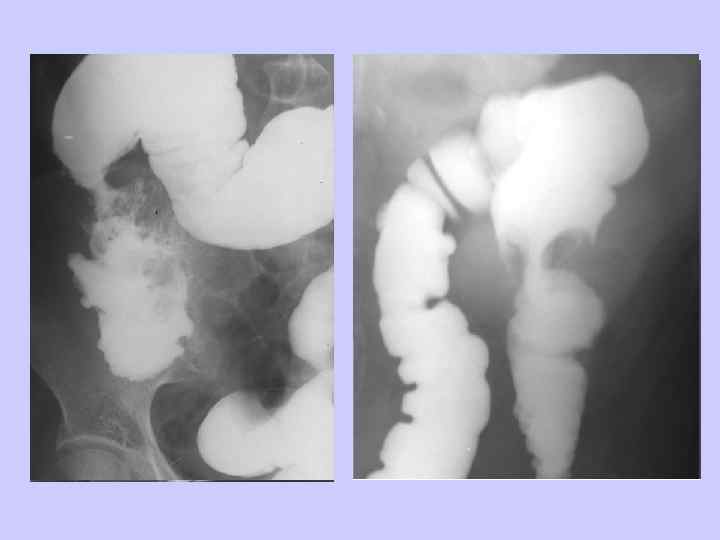

ДИАГНОСТИЧЕСКИЙ АЛГОРИТМ • • • Пальцевое исследование прямой кишки Ректосигмоидоскопия Ирригоскопия Колоноскопия Гистологическое исследование